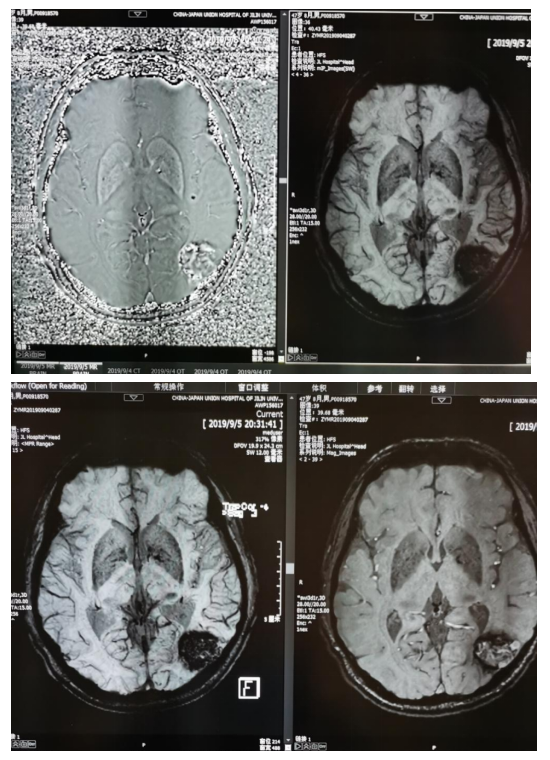

SWAN(磁敏感成像)动静脉畸形

头部MRA正常 颈部MRA左侧椎动脉纤细